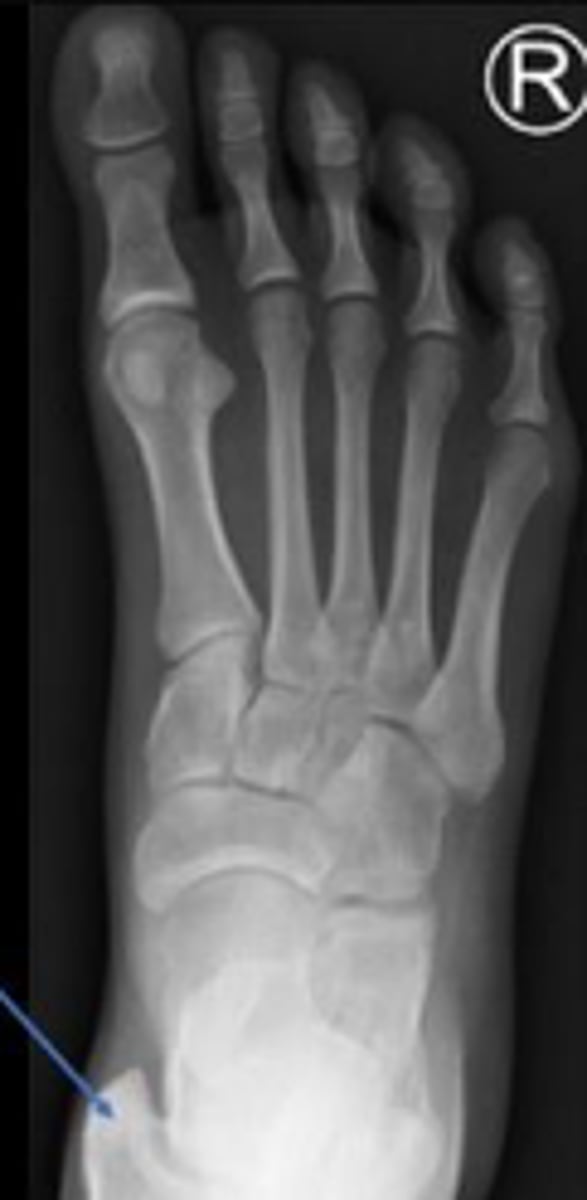

Medial oblique of the left foot

What is the name of the radiographic view?

Navicular of the right foo

What is outlined?

Medial malleolus of the right foot

What is the arrow pointing to?

Navicular of the left foot

What are the arrows pointing to?